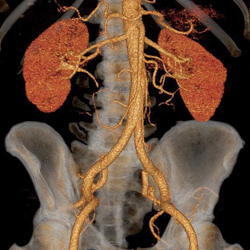

Computertomographie

Mehrzeilenspiral CT

Die Computertomographie(CT) ist eine spezielle Röntgenuntersuchung, bei der ein Volumendatensatz mit sehr dünnen (0,5mm) Querschnittsbildern jeder beliebigen Körperregion mit einer sehr hohen räumlichen Auflösung bei hohem Kontrast erzeugt werden können.

Gefäßuntersuchungen, 3D Darstellungen, CT gesteuerte Interventionen:

Gefäßerweiterungen (Aneurysmen)